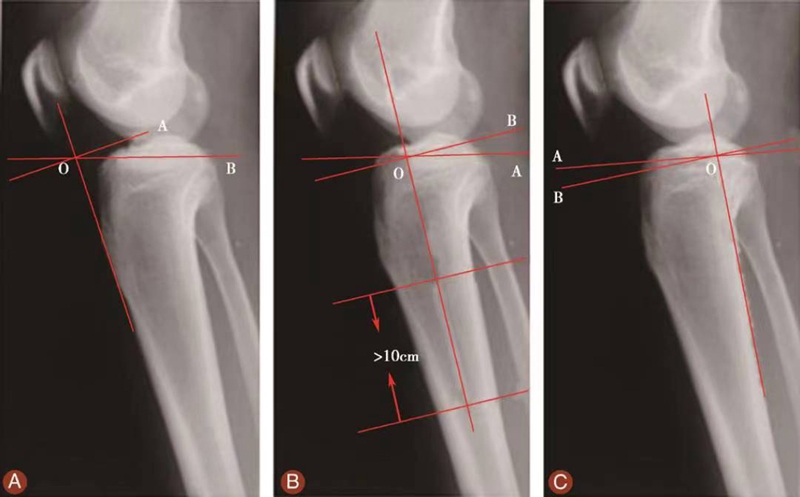

3 胫骨后倾角的评估

测量胫骨后倾角时先要观察胫骨上段及其与腓骨的位置关系,选择无明显胫骨旋转的,胫骨平台轮廓清晰的膝关节X侧位片。方法1测得的胫骨后倾角范围是11.74°±3.87°,方法2测得的胫骨后倾角范围是8.91°±3.57°,方法3测得的胫骨后倾角范围是6.21°±3.51°。

图15 胫骨后倾角的评估

用量角器测量胫骨内侧平台前后缘连线分别与胫骨中上段前侧骨皮质切线的垂线(图15A)、胫骨结节下胫骨中上段轴线的垂线(图15B)以及胫骨后侧皮质切线的垂线(图15C)的夹角,即胫骨后倾角(∠AOB)